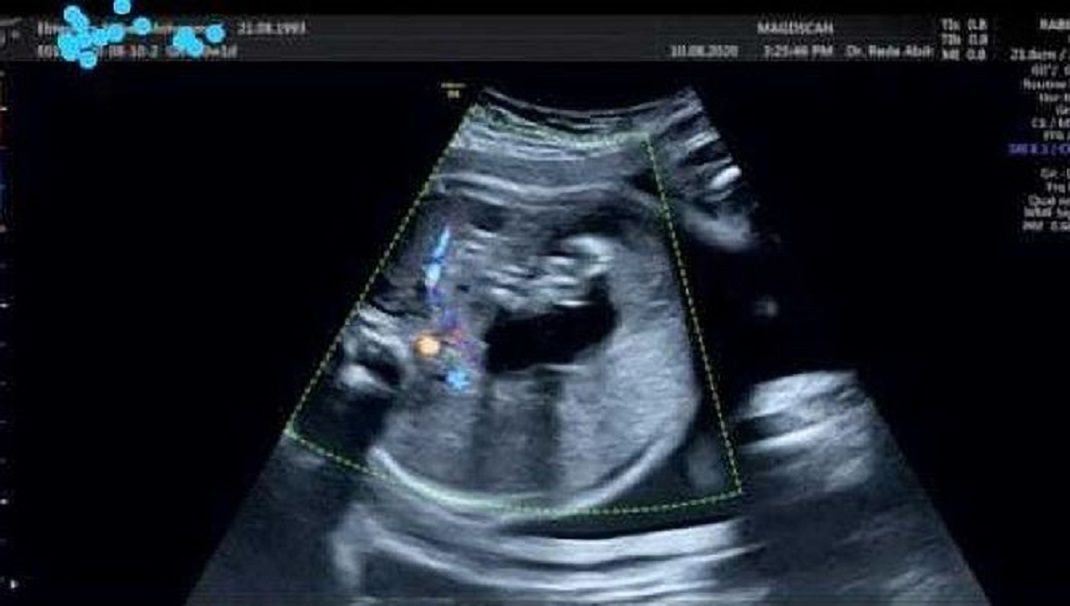

Opisano jedynie 200 przypadków

Jak zaznaczają autorzy artykułu, wewnątrzczaszkowy płód w płodzie powstaje z nierozdzielonych blastocyst, czyli wczesnego stadium rozwoju zarodków. Następnie pobiera z układu krwionośnego zdrowego bliźniaka substancje odżywcze, dzięki czemu może rosnąć. Jednak jest to tak powolny proces, że nawet osoby dorosłe nie wiedzą, iż mają w ciele pasożytniczego bliźniaka.

Jest to jednak bardzo rzadkie zjawisko i jak dotąd opisano jedynie 200 podobnych przypadków. W 1982 roku brytyjscy naukowcy opisali przypadek niemowlęcia, któremu usunęli 14-centymetrowy płód z czaszki. Szczęśliwie operacja zakończyła się sukcesem, a dziecko wróciło do zdrowia.